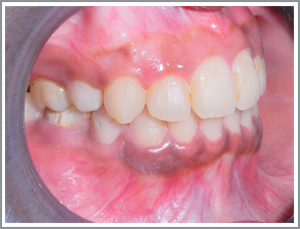

Before

After

JKL a 15 year old boy had severe crowding of teeth (Angles class I malocclusion with crowding)

Problem list : unsightly appearance of teeth and recession of the gums due to outward projection of the canines.

Treatment plan : Extraction case - The case was treated with extraction of four first premolars and the alignment of the canines into the extraction spaces. The canines are very rarely extracted. They are usually aligned by extracting premolars since they are crucial for normal functions like biting and also very important for the pleasing appearance of the teeth.

Treatment time : 15 months